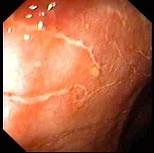

问题 男性,32岁,反复解黏液脓血便2年,查体:轻度贫血貌,心肺腹未见异常,大便常规示红细胞(++),白细胞(++),内镜图片如下,诊断 ( )

选项 A.直肠炎 B.放射性肠炎 C.慢性结肠炎 D.溃疡性直肠炎 E.直肠癌

答案 D